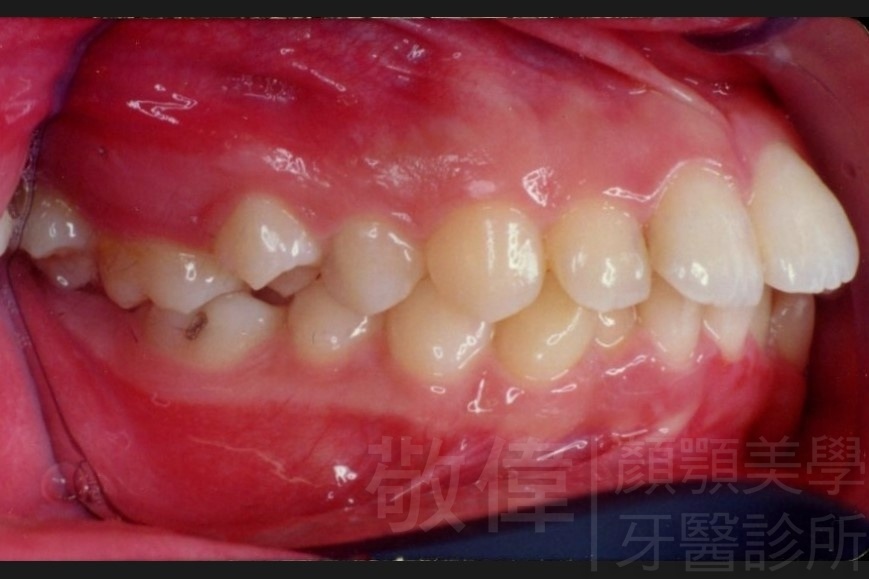

齒顏矯正/上顎暴牙且牙齒極度混亂

矯正前-右   矯正前-正   矯正前-左

矯正後-右   矯正後-正   矯正後-左

<個案說明>

上顎暴牙且牙齒極度混亂,經由矯正之後,臉型大幅度改善,牙齒的排列更加的整齊健康。相較於之前眼神充滿精神,自信心展現無遺。